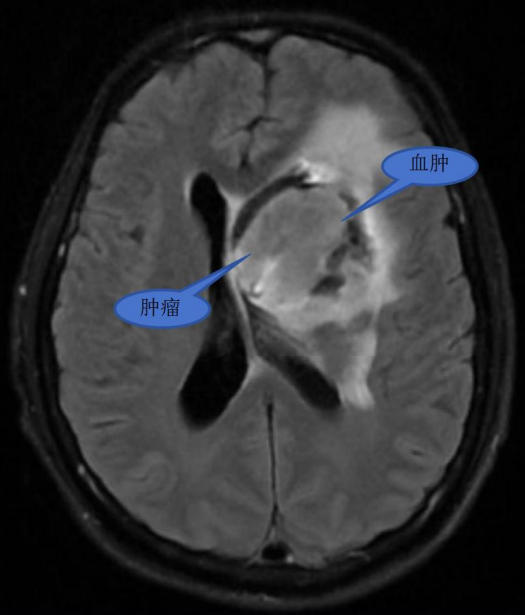

患者为 58 岁男性,因突发右侧肢体乏力 2 小时入院。急诊 CT 检查结合病史与影像学分析,诊断为脑肿瘤卒中,肿瘤大小达 4.3×3.6×2.9cm。入院后,王继斌副主任组织神经内科、肿瘤科、麻醉科、康复医学科等多学科专家,对病情及治疗方案进行深入评估讨论,获得患者及家属充分理解与支持。

术前影像